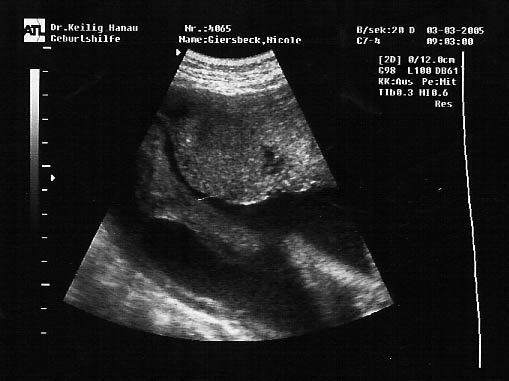

Meine Ultraschall-Bilder